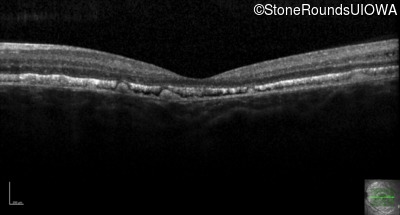

Age at visit: 23 years

This 15 year old girl came to medical attention during a routine athletic vision screening when the acuity in her right eye was observed to be abnormal.

Diagnosis & molecular findings

Best Disease BEST1 Asp228Glu GAC>GAG Asn259 ins2aacAA AR